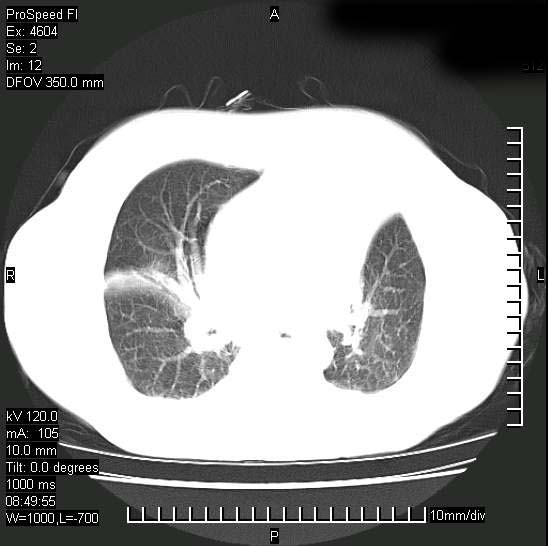

十几年前曾患肺结核,一周前突咳血约100ml,中性粒细胞稍高,诊断两上肺陈旧结核,下肺炎症,给予抗炎治疗,近几日晚上高热,39度,仍咳少量血,4天前ct及今天ct上传。

今天ct

支持陈旧性肺结核并两下肺感染,两侧胸腔积液。

短短几天内,病变范围明显增多扩大,以左侧明显,而且双侧出现胸水,还是考虑感染.

短短几天内,病变范围明显增多扩大,以左侧明显,而且双侧出现胸水,我更多考虑左侧中心性肺癌并并阻塞性不张及肺炎,炎症变化也太快了!

无论是肿瘤还是炎症4天的时间都发展够快的,并且还在治疗中,如果说是左肺癌那么右肺的病变不好解释,本人更加倾向于炎症,左肺舌叶支气管被痰栓或血凝块堵塞,造成阻塞性肺炎。

1)两肺结核并感染。2)不排除左肺上叶中央型肺癌并阻塞性肺炎、肺不张可能;建议行纤支镜检查。3)右肺门及纵隔淋巴结肿大。4)双侧胸腔积液。

陈旧性肺结核及左下肺不张,咯血后肺部感染,双胸腔积液,高热可能与痰液引流不畅有关。